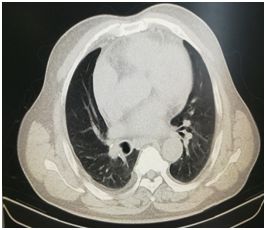

某女性患者,64岁,因咳嗽发热入住内科治疗,胸部CT提示右侧胸腔积液及右肺不张(图3),后转入我院胸外科治疗,经讨论后全麻下行胸腔镜检查,术中见壁层胸膜多发灰白色结节,遂行结节活检术,术后病理诊断为胸膜结核,予以正规抗痨药物治疗,6个月后复查胸部CT,积液消失,肺部情况良好(图4),目前仍在随访中。

图3